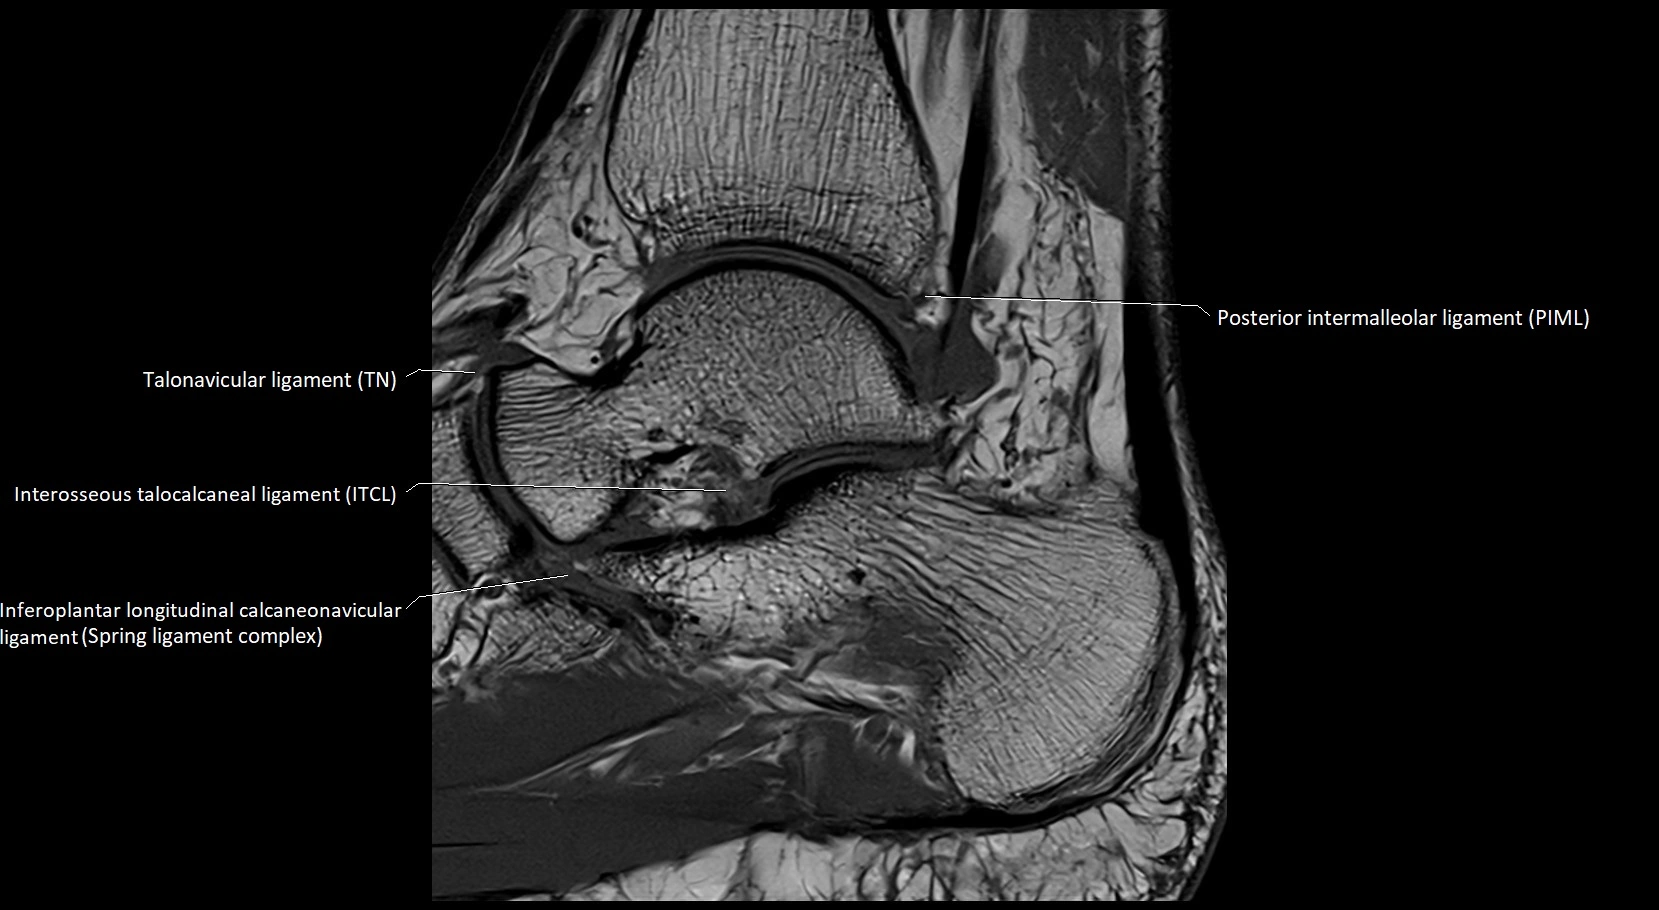

MRI image

image